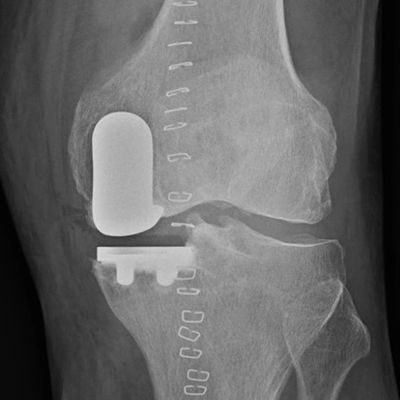

Knee replacements resurface the worn ends of the knee joint. The metal implants are cemented in place using special bone cement. Between the two metal implants there is a hard wearing plastic insert.

Total knee replacements resurface the entire knee joint, while partial knee replacements only replace the worn side.

Total knee replacement surgery resurfaces the entire knee joint. Both ends of the joint are replaced with metal implants that are cemented in place using special bone cement. The worn surface of the kneecap (patella) is resurfaced using a plastic button.

Partial knee replacement is where only one of the compartments of the knee is replaced, most commonly the inside (medial).